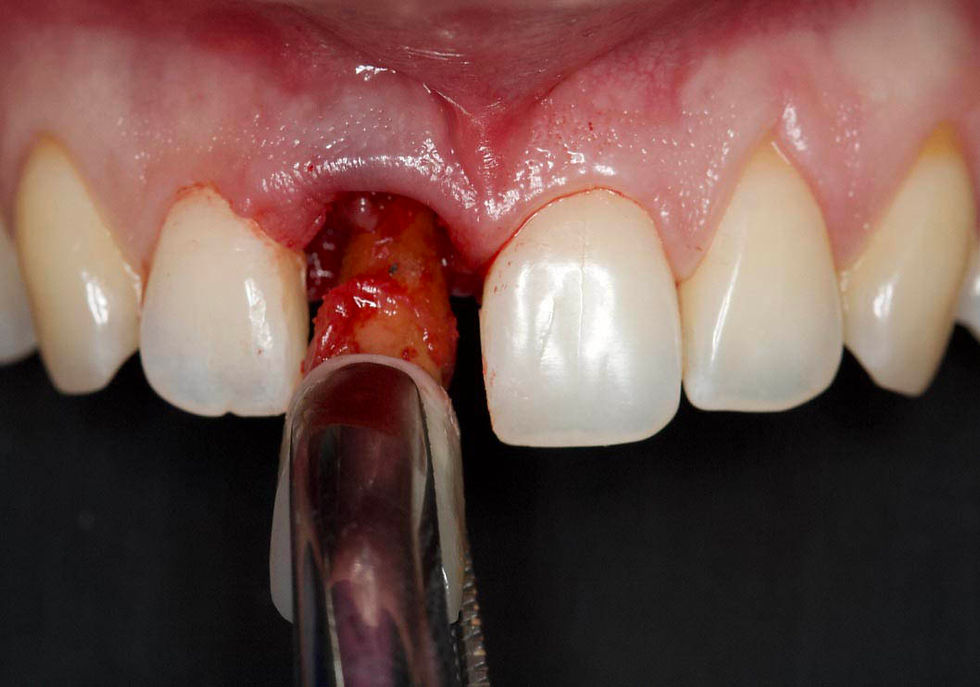

Extraction of the element in a non-traumatic way.